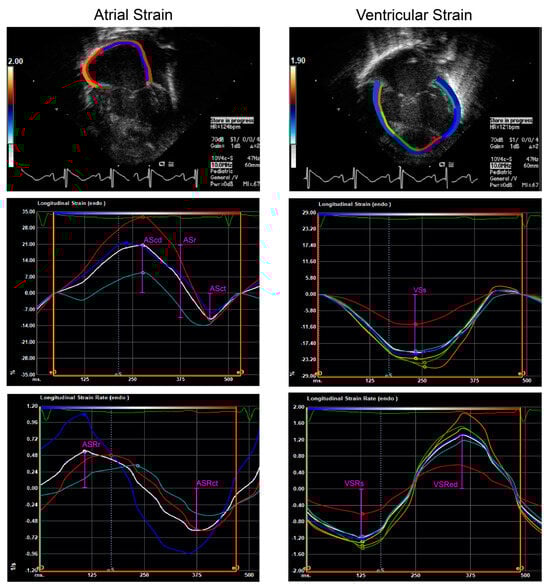

2.3. Myocardial Strain

3.3. Right Atrial and Ventricular Strain Analyses

4. Discussion